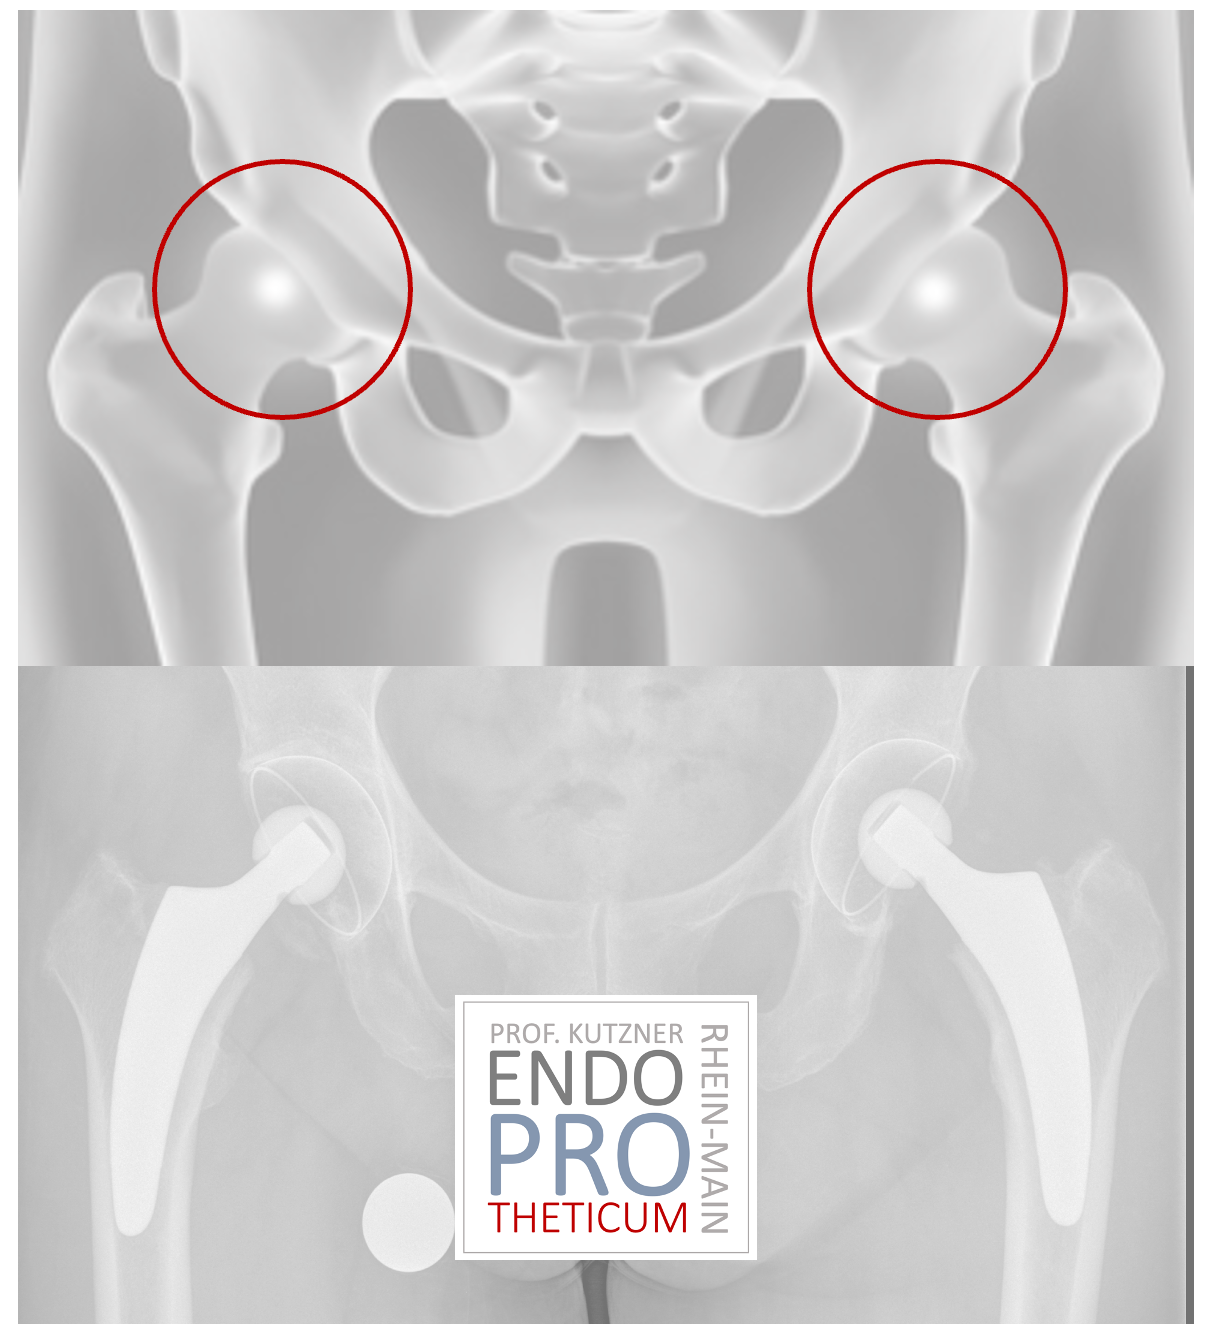

THE ENDOPROTHETICUM, YOUR endoprosthesis center IN MAINZ, specializes in the treatment of patients with joint diseases. It offers comprehensive care and treatment for people who suffer from joint pain and discomfort.

First of all, an endoprosthesis center LIKE THE ENDOPROTHETICUM IN MAINZ offers highly specialized care. PROF. KUTZNER HAS extensive training and experience in the treatment of joint diseases. HE IS familiar with the latest medical techniques and procedures and CAN make an accurate diagnosis and develop a customized treatment for each patient.

Another important aspect is the availability of the latest medical equipment and facilities in an endoprosthesis center. From advanced imaging techniques to state-of-the-art operating rooms, endoprosthesis centers, LIKE THE ENDOPROTHETICUM, are equipped with everything needed for successful treatment.

Overall, it is important for patients to visit an endoprosthesis center because it offers highly specialized care, state-of-the-art medical procedures AND comprehensive aftercare.